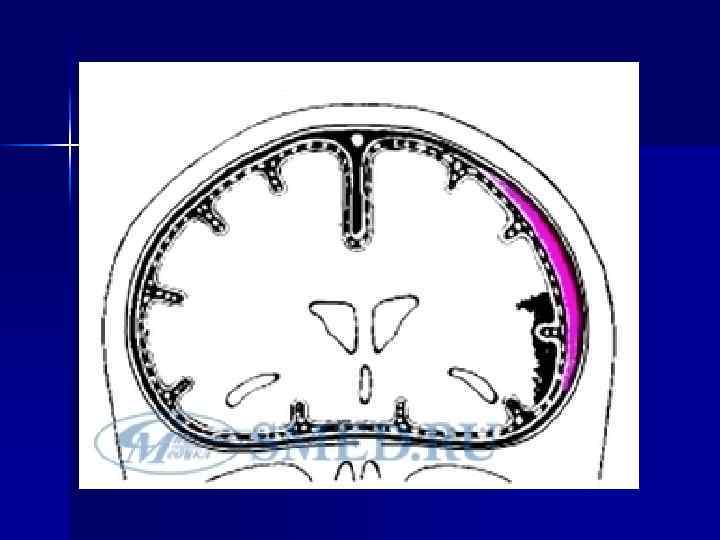

Схема эпидуральной и субдуральной гематом